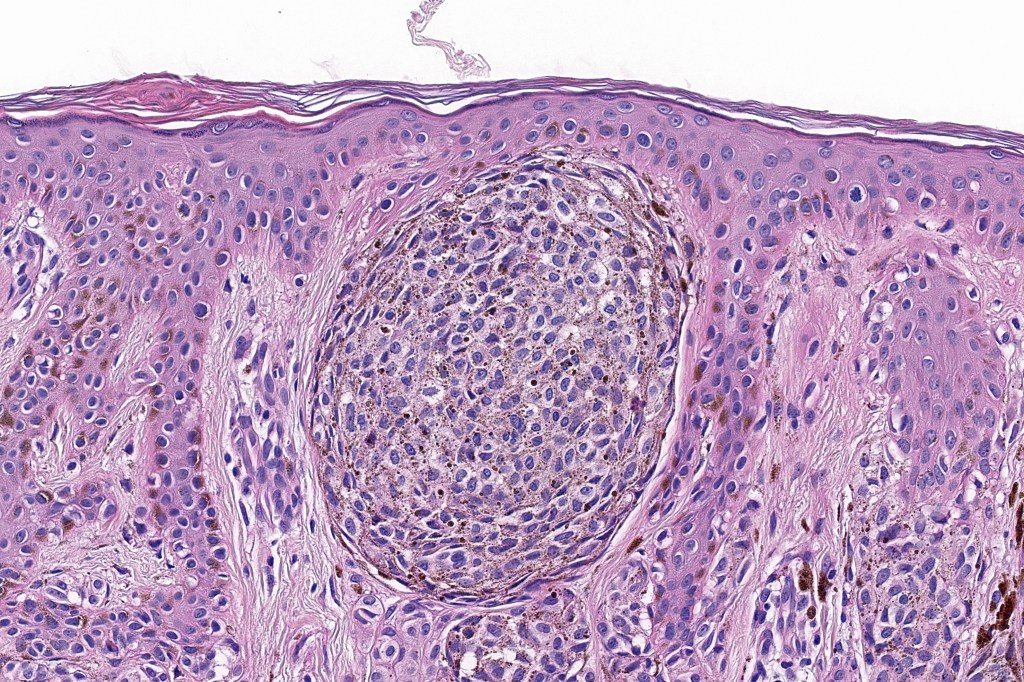

Combined Spitz & common blue nevus